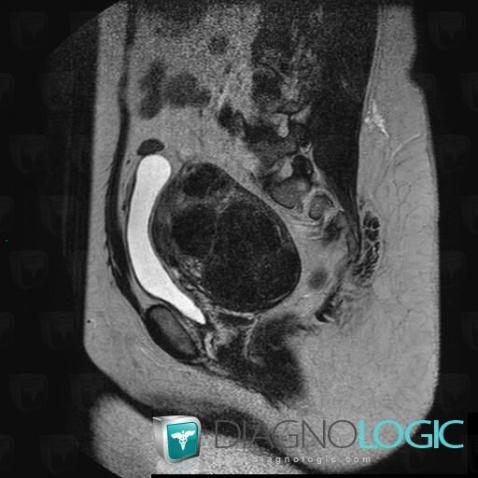

Leiomyoma, Uterus, MRI

Here is the specific information in the key image above:

- Diagnosis Leiomyoma, Location(s) Uterus, with gamuts Myometrial lesion, Uterine mass